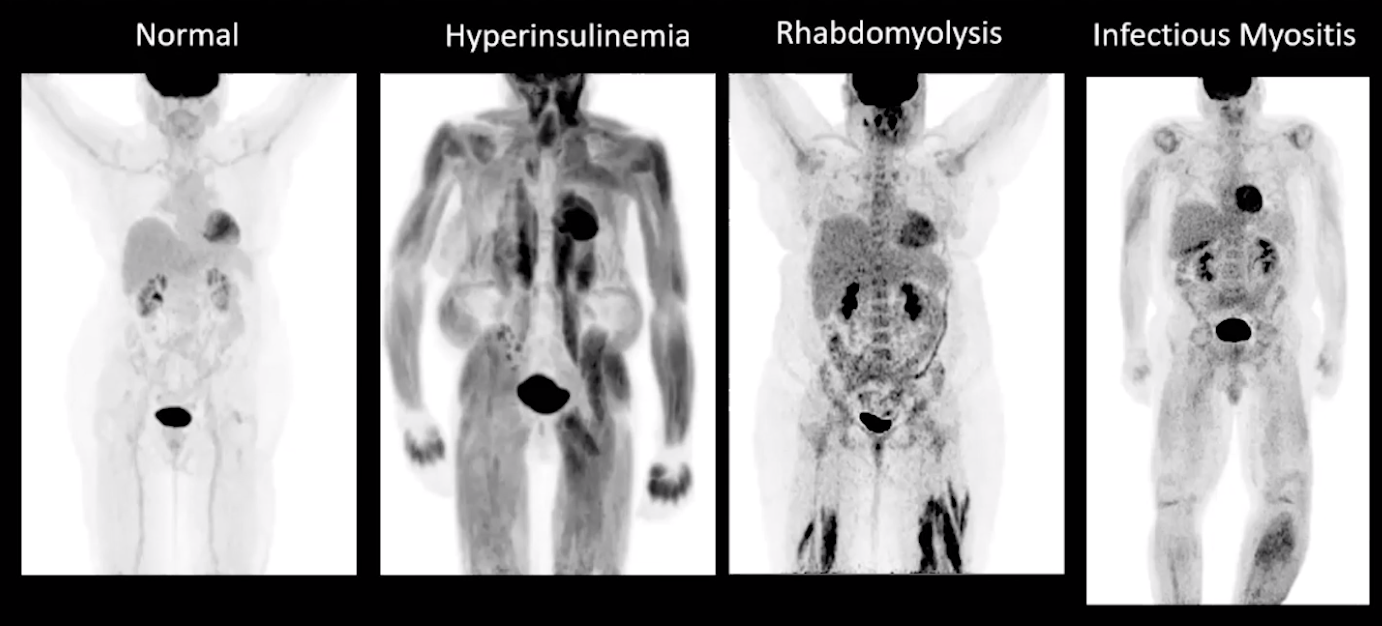

• Insulin causes increased muscle uptake of glucose

• Need to time the insulin use in diabetics before PET is obtained

• Note you can have hyperinsulinemia with a normal glucose level, classically if a person recently ate a few hours before the exam the glucose will likely be normal but insulin will be high

• Ideally want glucose between 70-200

• When insulin is high then the glucose will be diverted to other areas and falsely dilute its transport to the cancer so even if the cancer is hot it is likely not as hot as it should be because the glucose tracer is being diverted to muscle and other areas

• Avoid exercise at least a day before scan —> causes increase glucose uptake by muscles